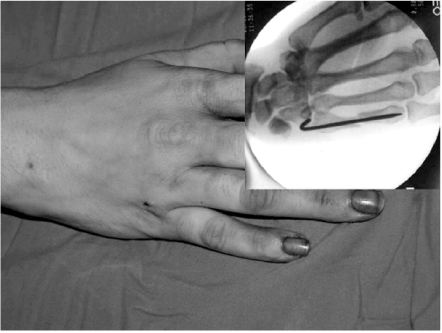

Fig. 5

Pin was migrated to the metacarpophalangeal joint in postoperative 4 weeks (A). After 6 months, complete bone healing occurred without loss of reduction (B).

The average follow-up period was one year nine months, with a range of 12~42 months. Average operation time was 18 minutes (range, 12~27 min) and no immediate complication was seen. Rotational malalignments were detected in 4 cases preoperatively and they were corrected by manual reduction without any further invasive procedure. Distal migrations of K-wire tip to the MP joint were seen in two patients during the follow up. One patient showed migration in postoperative 3 weeks and the other in 4 weeks (Fig. 5). Migrated pins were removed immediately at the time of detection and gentle ROM exercise was recommended within the splint.

Good results have been reported for the other intramedullary technique with excellent fracture healing, good cosmetic results and few complications4,13), and our series adds merit to this method of fixation. But authors realized that pin migration could make serious complication to the joint unless it is not managed appropriately. Bent proximal wire tip should be located close to the metacarpal base during the procedure for prevention of this problem. Author's all pin migrated patients had longer proximal tip and even small motion of wrist could make the pins migrate.